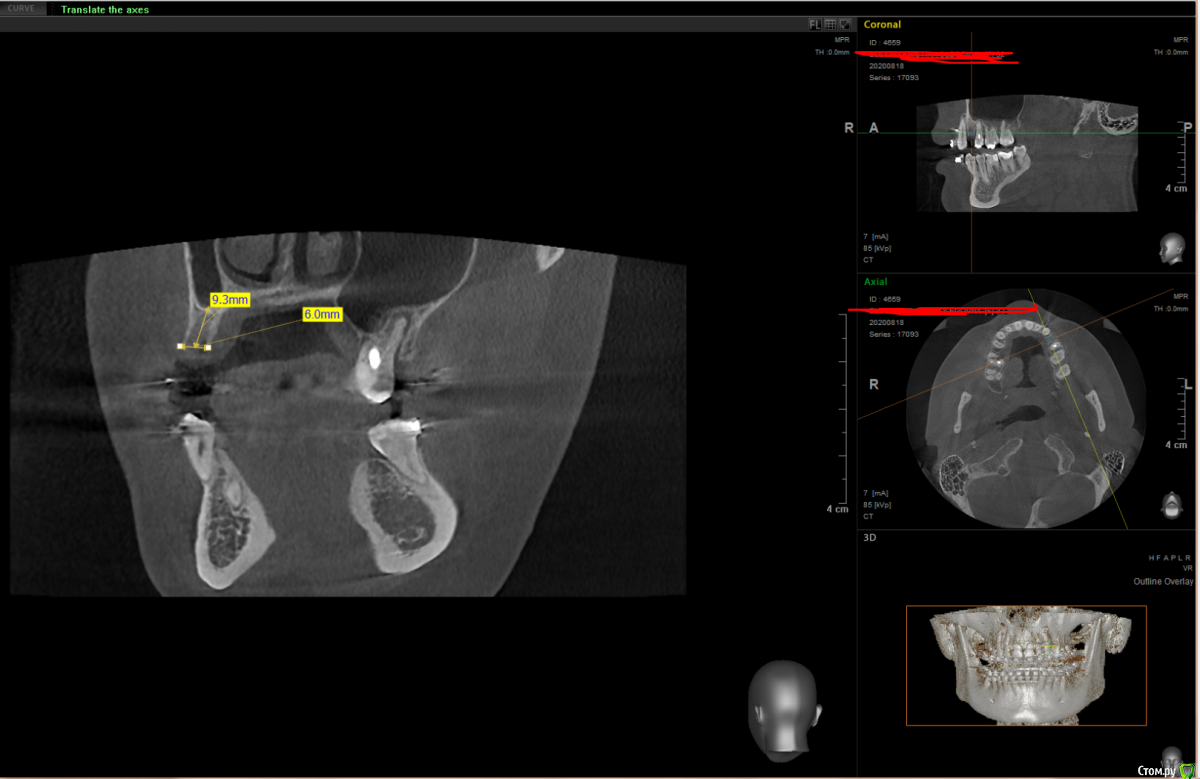

It'sGeorgy Опубликовано 19 ноября, 2020 Поделиться Опубликовано 19 ноября, 2020 Здравствуйте.Вот такая ситуация:Ставить планирую по шаблону с направляющей фрезой из Пикассо. Дополнительно ССТ с неба. Не могу определиться с имплантатом:Straumann BLT 2.9x10 или Straumann BL 3.3x10Производитель не рекомендует 2.9 на премоляры, но тут и размер коронки меньше, чем у стандартного премоляра. С другой стороны, жевательным зубом он быть от этого не перестает.Что посоветуете? Ссылка на комментарий

It'sGeorgy Опубликовано 19 ноября, 2020 Автор Поделиться Опубликовано 19 ноября, 2020 Ширина кости, в первую очередь. После установки диаметра 3.3мм останется по 1.3мм вестибулярно и орально. На мой взгляд, это очень близко к минимальной допустимой ширине стенок. Собственно, из этого и появились сомнения: может пожертвовать 0.4 титана, поставив диаметр 2.9, и получить лишние 0.4 кости. Опять же, небольшой размер коронки на это так же подталкивает. Вы бы поставили 3.3? Ссылка на комментарий

Bier Опубликовано 19 ноября, 2020 Поделиться Опубликовано 19 ноября, 2020 показания для 3.3 2 Ссылка на комментарий

Nazim_NV86 Опубликовано 22 ноября, 2020 Поделиться Опубликовано 22 ноября, 2020 (изменено) Здравствуйте.Вот такая ситуация:1.png2.png3.pngСтавить планирую по шаблону с направляющей фрезой из Пикассо. Дополнительно ССТ с неба. Не могу определиться с имплантатом:Straumann BLT 2.9x10 или Straumann BL 3.3x10Производитель не рекомендует 2.9 на премоляры, но тут и размер коронки меньше, чем у стандартного премоляра. С другой стороны, жевательным зубом он быть от этого не перестает.Что посоветуете?Смотрите не на толщину кости, а на свои возможности. Если бы апроксимально место позволяло, я бы и 4.1 пристроил. Если под рукой есть диск или пьезо + экспандеры, то сделать +1-1.5мм вестибулярно вообще не проблема на ВЧ. Изменено 22 ноября, 2020 пользователем Nazim_NV86 1 Ссылка на комментарий